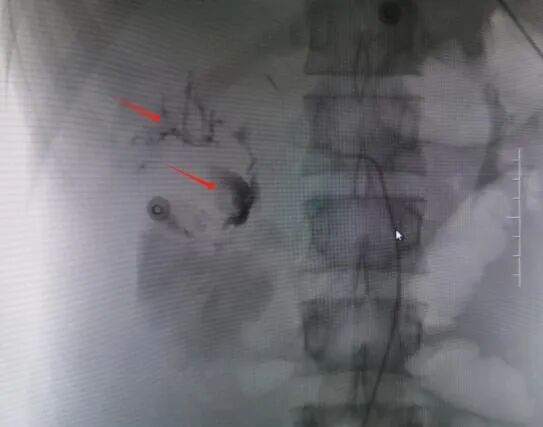

术前DSA造影图,红色箭头指示为出血点

救治方案明确后,患者立即被推入了手术室,在邓文军总监的指挥下,一场惊心动魄、紧张有序的手术开始了。各专科主任严阵以待,在院待命,随时做好开腹手术准备。介入手术由影像中心副主任兼介入组组长吴继雄主任医师亲自主刀,手术过程顺利,术中造影找到右肾脏有几处明显的活动性出血点,肝脏也有两处活动性出血点,给予及时栓塞止血后,再次造影无明显出血。整个手术仅约一个小时,刀口仅针眼大小,术中病人情况稳定,失血量不到10ml,患者成功脱离生命危险,术后被送入ICU密切观察诊治。病情平稳后转入普通病房,经过后续治疗目前该患者已经平安出院,出院时状态良好已经能自行走路。